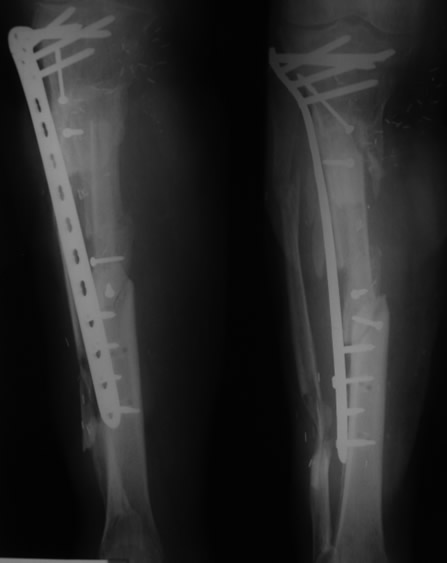

Se retiró el fijador externo a los dos meses y se sustituyó por una placa de osteosíntesis para permitir la rehabilitación simultánea de la rodilla.

03. Resultado

El resultado funcional fue satisfactorio con preservación de la pierna. Ausencia de dolor y deambulación correcta a los 12 meses del accidente. Un caso que demuestra que el aplastamiento severo no implica necesariamente la amputación cuando se aplica la técnica reconstructiva adecuada.